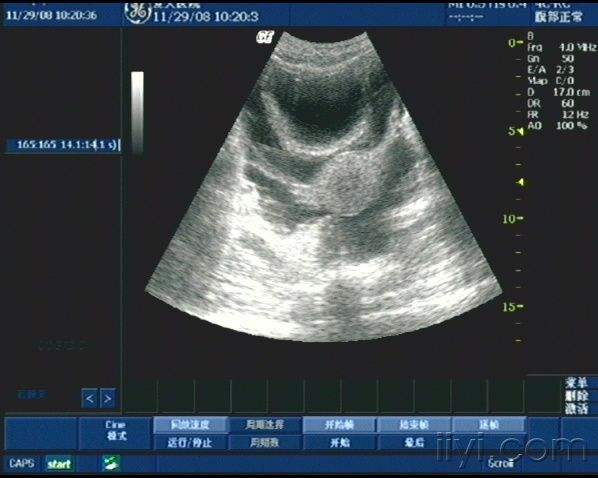

经典的转移性肝癌合并腹水(病理提示直肠腺癌)